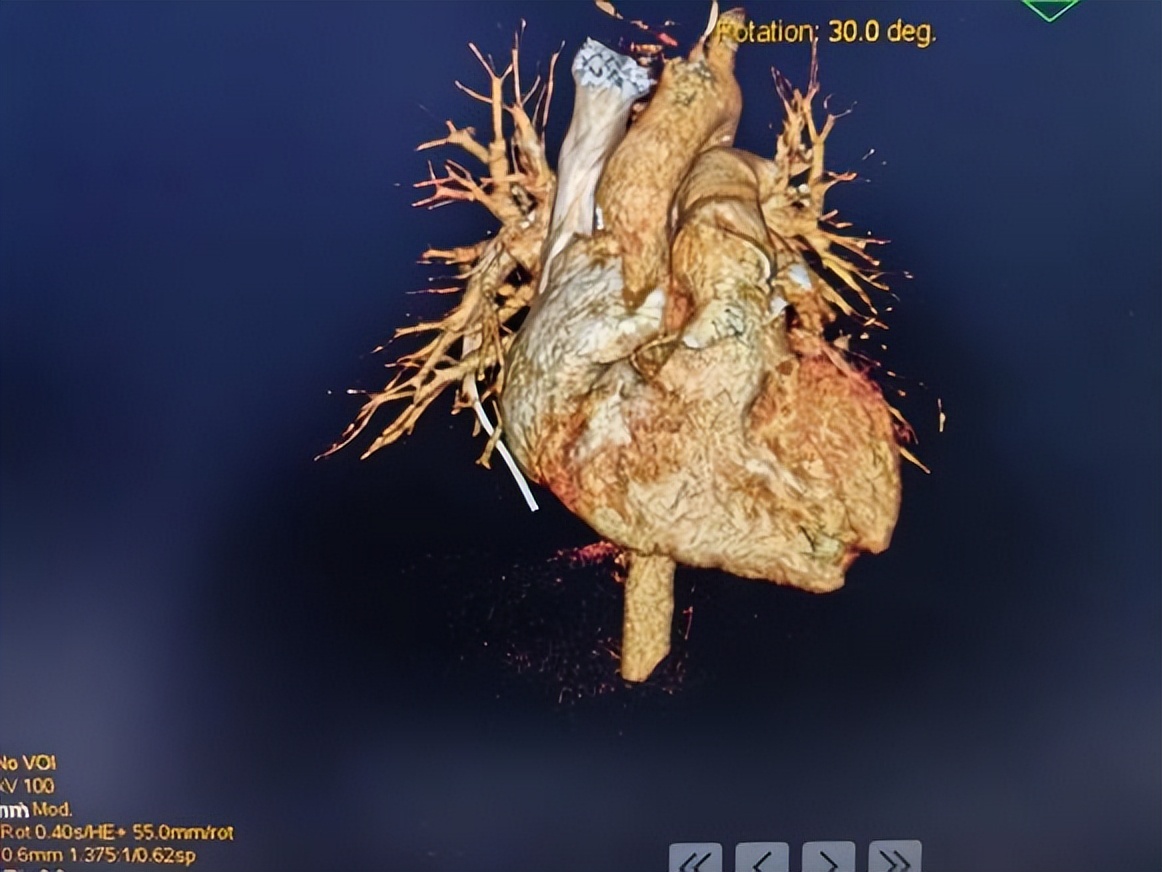

随后复查CT及三维重建显示:导管断裂,远端漂移至右下肺动脉。

术中发现断裂的PICC导管(箭头示)漂浮至右侧肺下动脉远端,一端飘浮在肺动脉干。

术中采用经皮血管内利用抓捕器抓捕住导管近端,轻柔拖拽导管,将断裂导管取出。